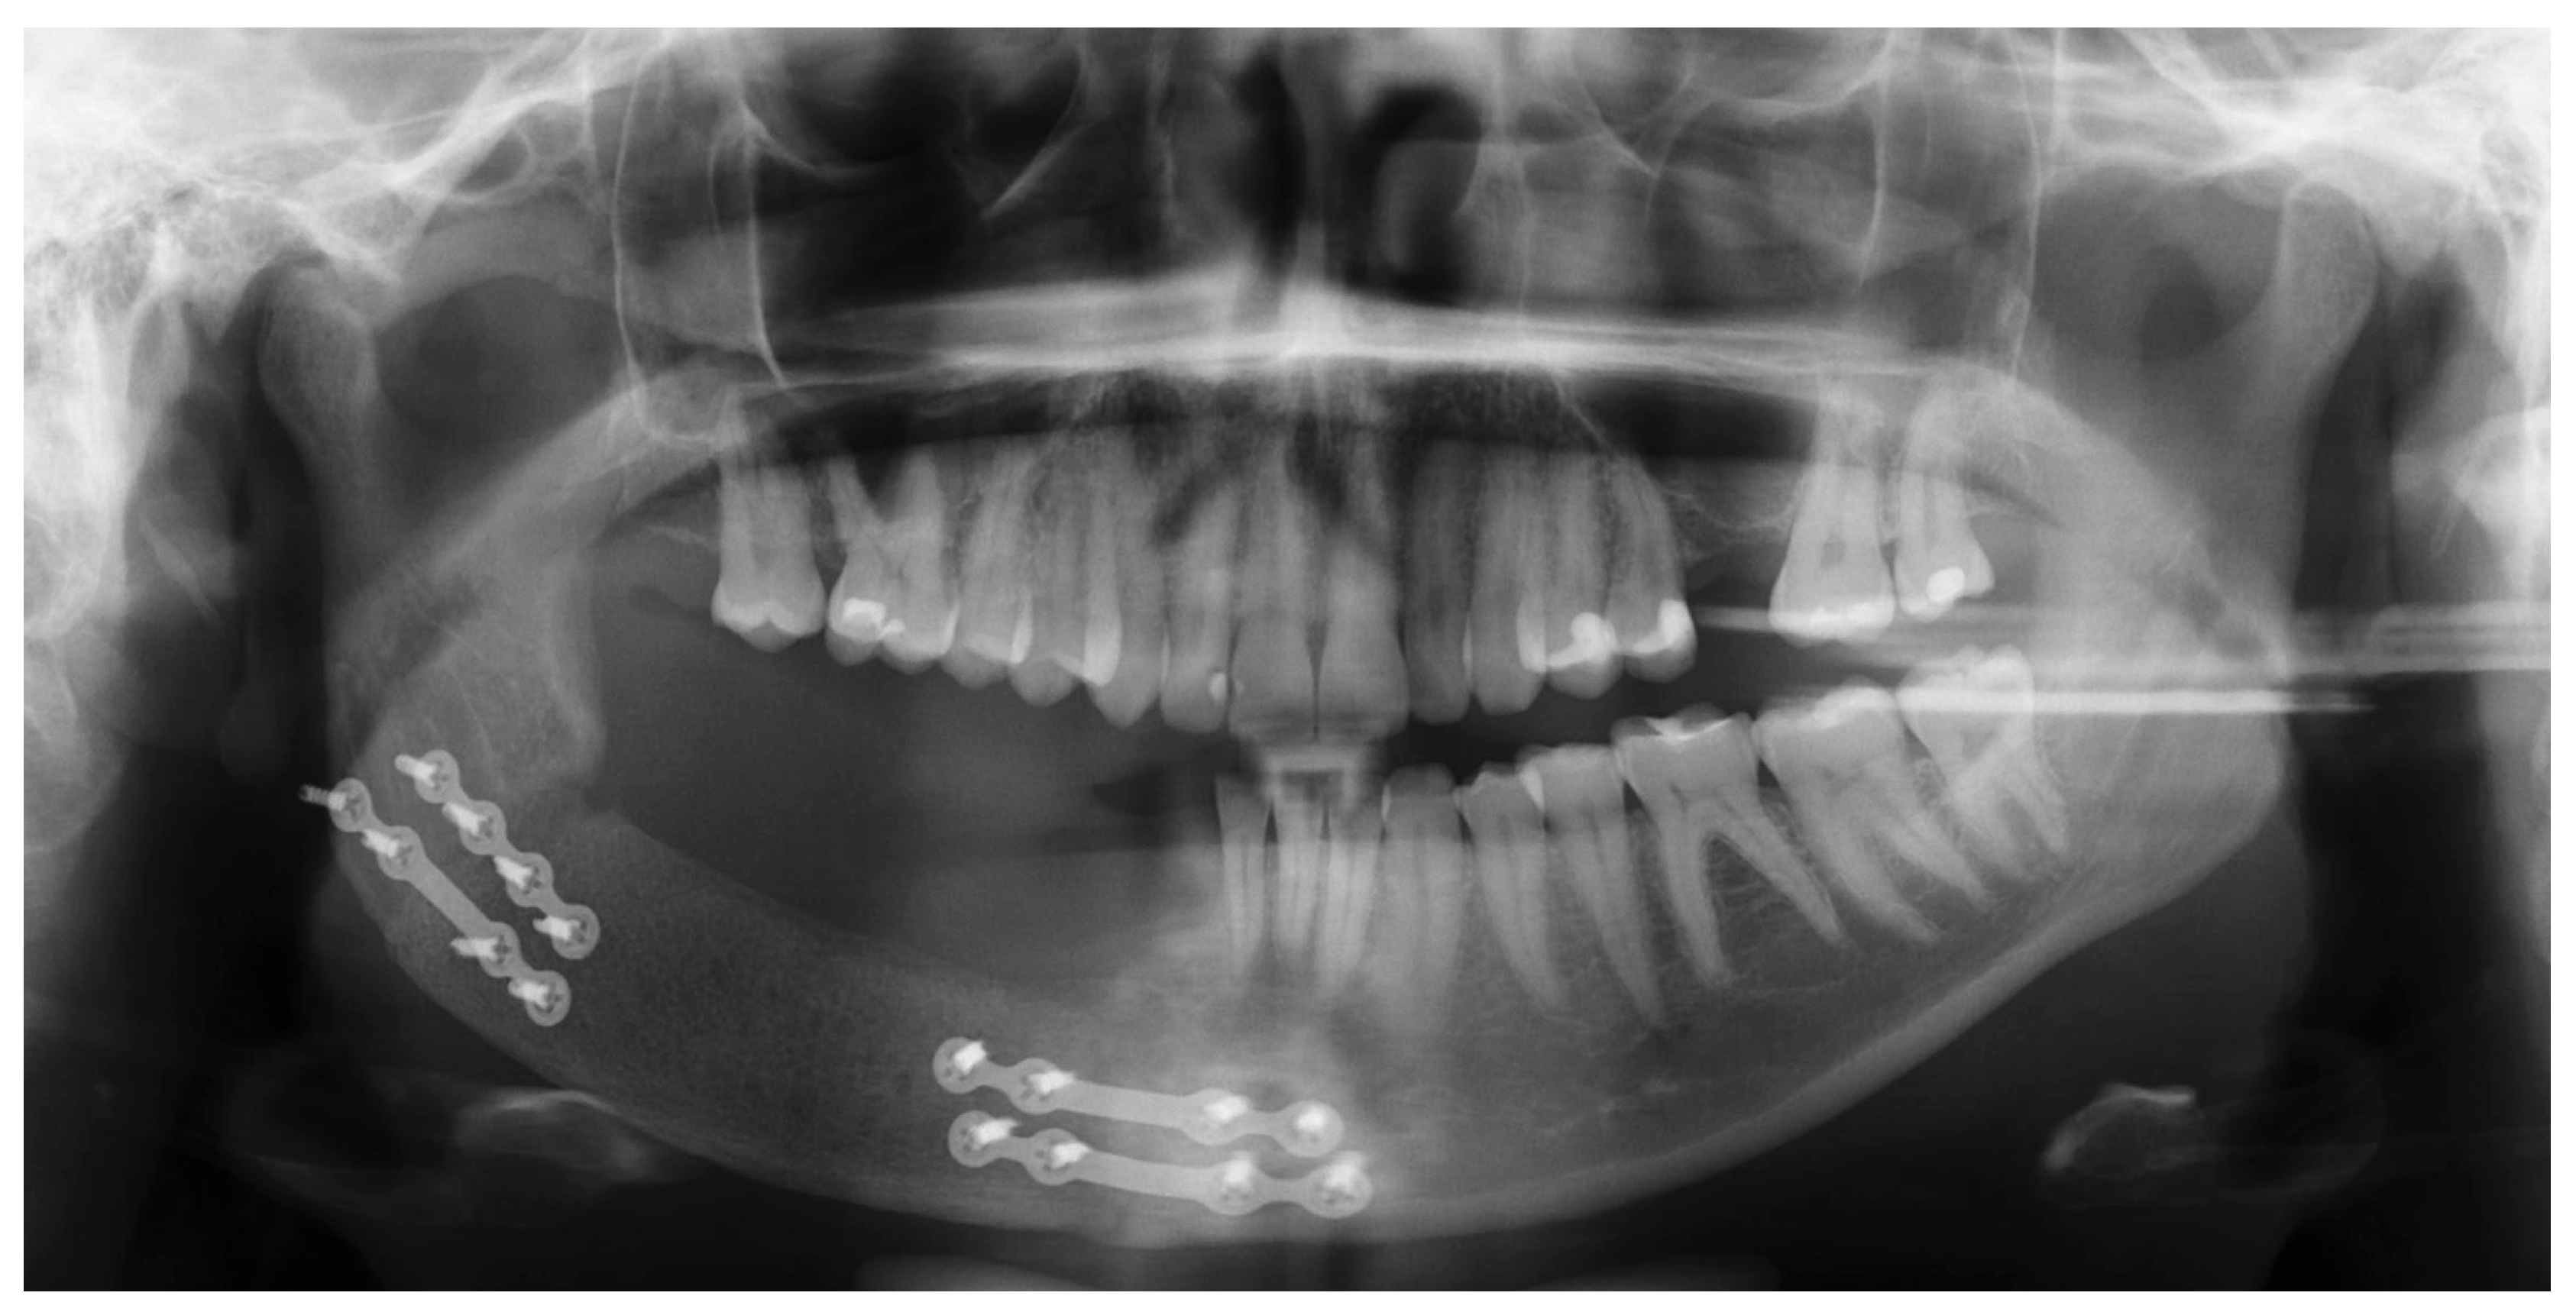

2.2. Treatment Procedures and Histopathological Results

| Radiographic | “Soap-bubble”, “ground-glass” or “tennis racquet strings” patterns complicating the diagnosis | [4,12,14] |